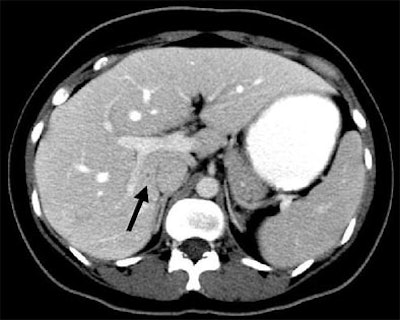

| Patient with fever after prolonged neutropenia. Above, arterial-phase CT of liver shows a type 2b lesion (arrow). Unenhanced CT (below) shows a corresponding hypoattenuating lesion, while portal-venous-phase CT (bottom) shows a tiny nonspecific hypodensity (type 1 lesion). This case demonstrates how arterial-phase CT adds specificity. Although portal-venous phase depicted the lesion, it would be extremely difficult to "call" it an abscess. The enhancement pattern on arterial phase CT makes for a more confident diagnosis. All images courtesy of Dr. Ur Metser. |

![]() |